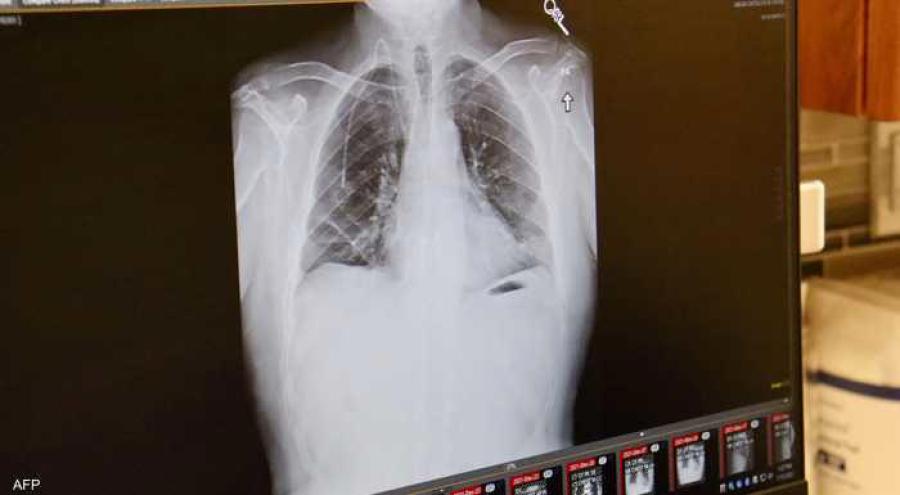

كشفت دراسة علمية أن تلوث الهواء يرتبط بشكل وثيق بطفرات في الحمض النووي مرتبطة بسرطان الرئة، حتى لدى الأشخاص الذين لم يسبق لهم التدخين.

وشملت الدراسة فحص الجينومات السرطانية لـ871 مصابا بسرطان الرئة من 4 قارات، جميعهم لم يسبق لهم التدخين ولم يتلقوا علاجا للسرطان بعد.